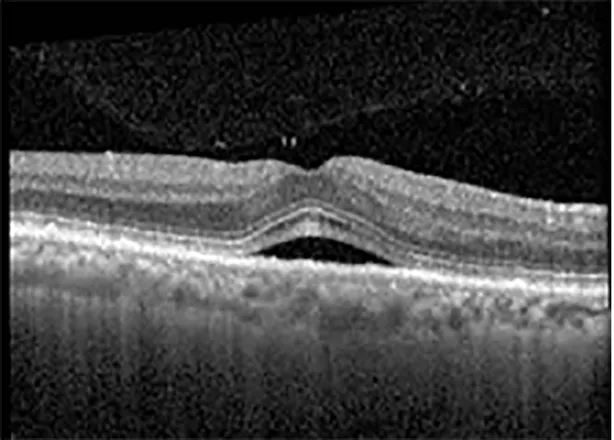

The patient began treatment with oral pemigatinib daily and was followed up for an ophthalmic examination during the second treatment cycle approximately 5 weeks into the treatment process. The patient had at this stage received 28 doses of 13.5 mg per day, which was administered in cycles of 14 on-days and 7 off-days, and had no visual or ophthalmic complaints. The non-corrected VA was OD 20/30 + 1 and OS 20/20. The OCT examinations revealed subfoveal SRF bilaterally. The fundus examination was otherwise unremarkable outside the patient’s prior documented peripheral drusen. Repeat autofluorescence was overall unchanged, though a slight hypofluorescent ring may be visualized in Figure 2. The current pemigatinib protocol recommendation for asymptomatic patients suggests no dose modification; however, with worsening presentation or positive symptoms, it is recommended to withhold pemigatinib. After discussion with the patient’s oncologist, it was decided to continue the medication at this time. Serial monitoring of the patient’s symptoms, vision, and SRF were conducted on specific days during active treatment cycles and days off-cycle to monitor the SRF. Subsequent evaluations demonstrated complete resolution of SRF while off-cycle, and asymptomatic re-accumulation of fluid while on-cycle with varying levels of VA. (Table 1) As we see demonstrated in the table below, in the later stages of the active cycles, such as day 13 of 14 of cycle 2, day 13 of 14 of cycle 3, day 13 of 14 of cycle 4, and day 14 of 14 on cycle 5, the patient’s VA showed no correlative changes based on the presence of SRF. The fluctuations in the patient’s VA certainly occurred, but were likely to be secondary to surface changes, as certain off-cycle days actually presented with lower acuities than days when the SRF was present on OCT examination.

Figure 2

| Cycle, day, on/off | VA OD; OS | CMT OD; OS | OCT OD | OCT OS |

| Cycle 2, day 13/14, on | 20/30+1; 20/20 | 365; 355 | ![]() | ![]() |

| Cycle 2, day 4, off | 20/30−2; 20/20−2 | 282; 280 | ![]() | ![]() |

Highlights the visual acuity, central macular thickness, and the physical OCT of the macula for this patient in both the right and left eyes during various stages of the patient's chemotherapy treatment cycle.